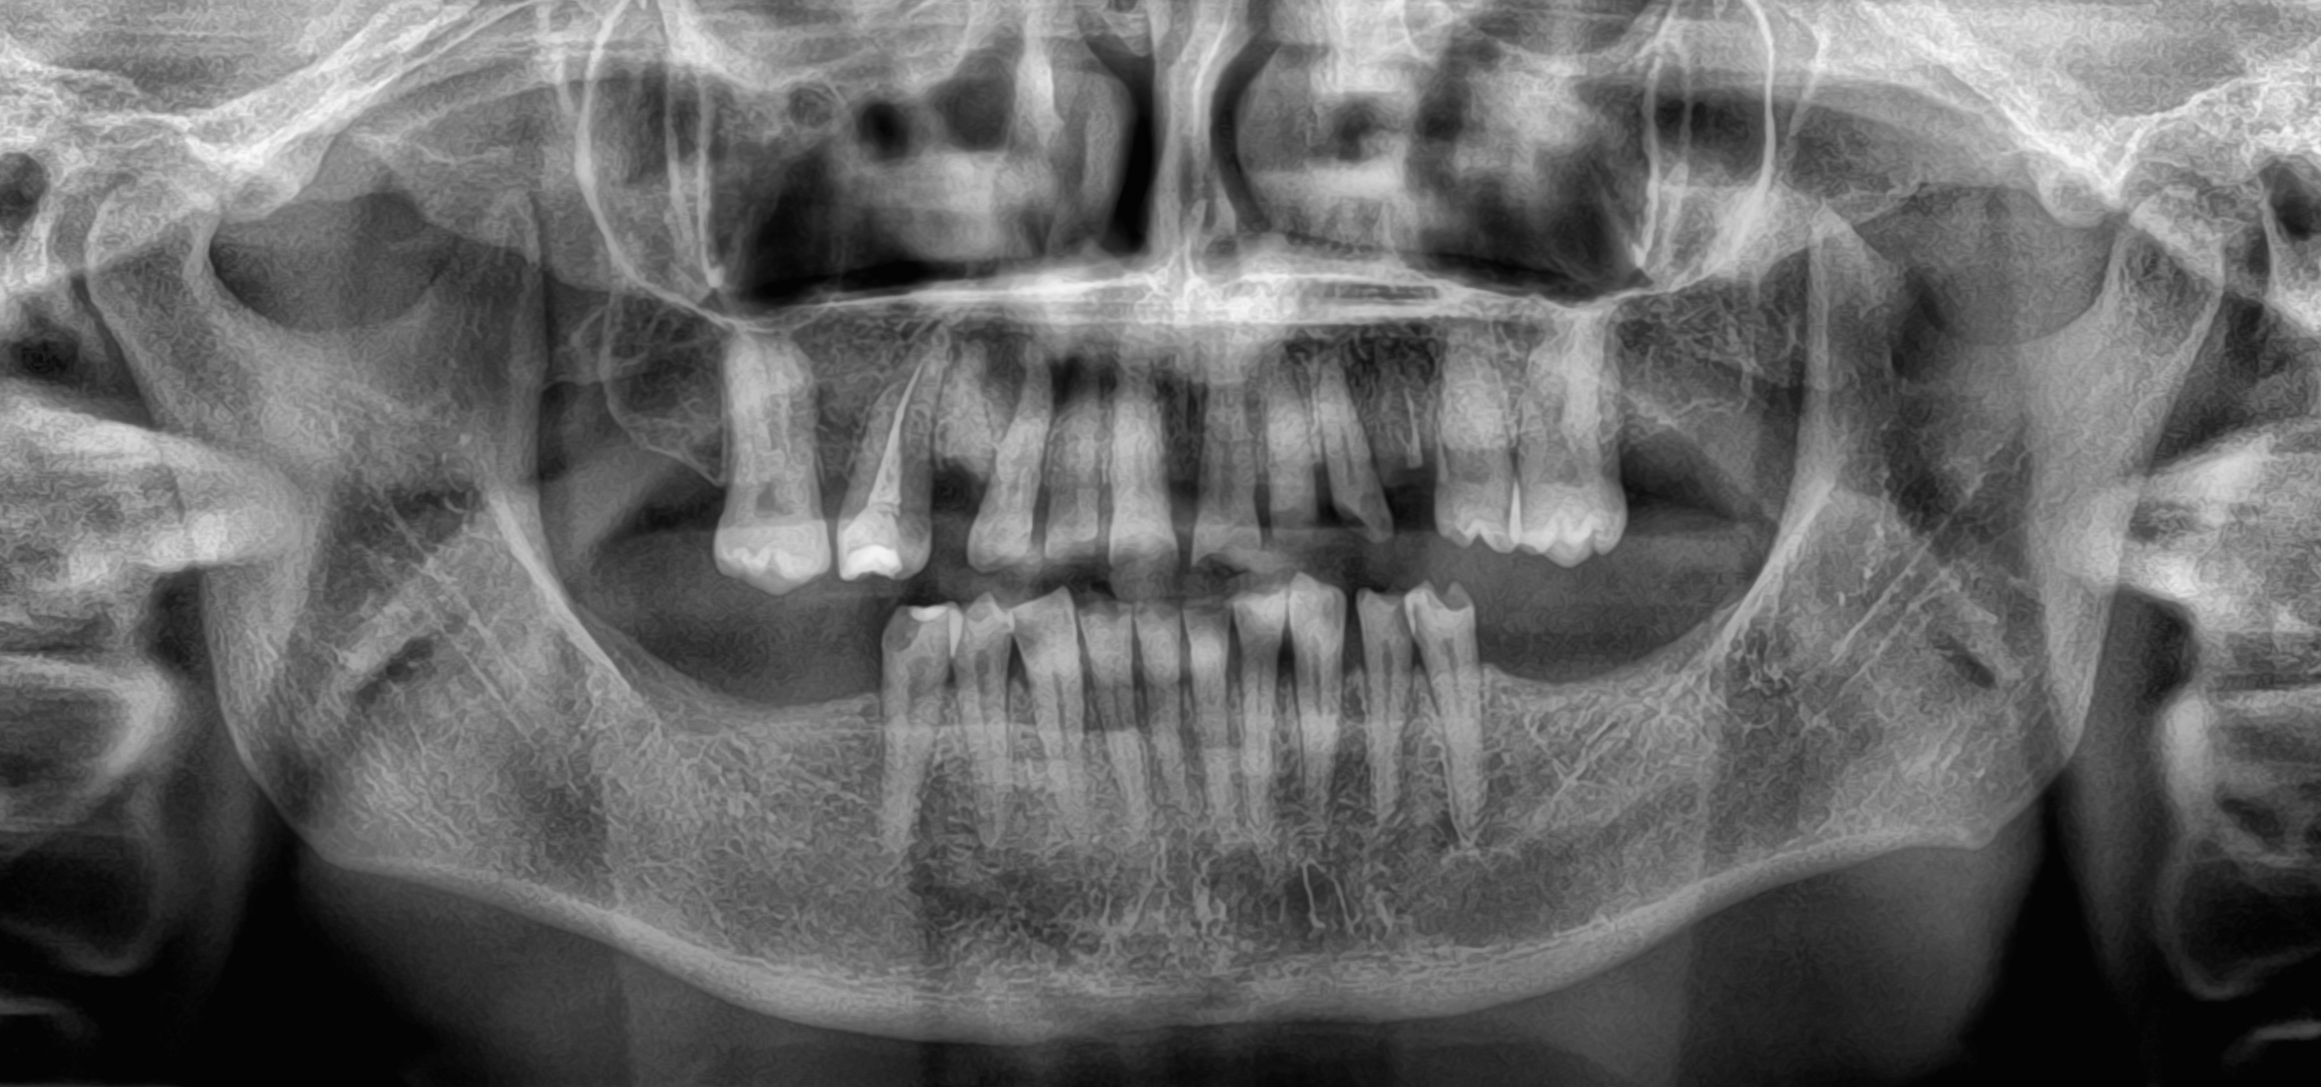

Ασθενής με αποδιοργανωμένη, εκτενώς φθαρμένη οδοντοφυΐα, τερηδόνες και κατεστραμμένα δόντια στην άνω γνάθο που προκαλούσαν έντονους πόνους, προσήλθε στο Aesthetic Dental Studio στην Καλαμάτα με στόχο την αισθητική και λειτουργική αποκατάσταση του στόματός της.

Σε πρώτη φάση, αφαιρέθηκαν τα δόντια που ήταν πλήρως κατεστραμμένα, πραγματοποιήθηκαν ενδοδοντικές θεραπείες στα δόντια που μπορούσαν να αποκατασταθούν και έγιναν εμφράξεις σε δόντια με απλή τερηδόνα. Έτσι, το στόμα σταθεροποιήθηκε και ήταν πλέον έτοιμο για την δεύτερη φάση της θεραπείας, που περιελάμβανε την προσθετική αποκατάσταση των δοντιών.